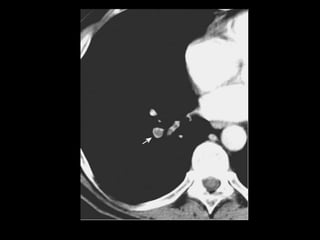

Mucormicose